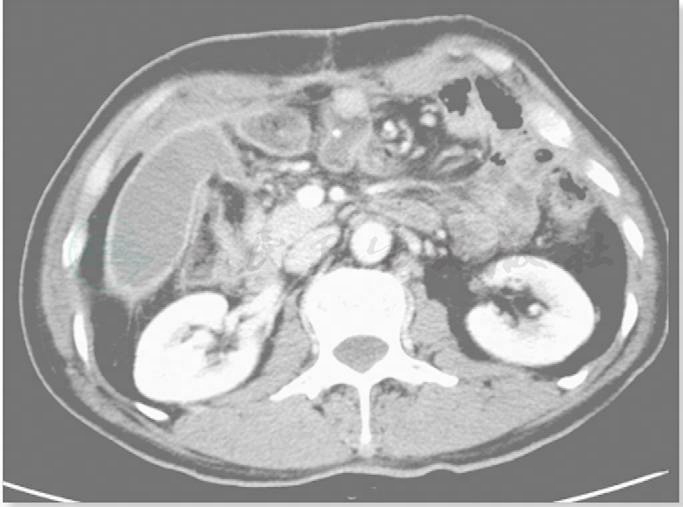

全腹部增强CT扫描:胃底、体部胃壁不规则增厚,浆膜面模糊不清,增强提示病灶明显强化改变,多系肿瘤性病变,扫及腹盆腔未见确切肿大淋巴结及积液。肝形态大小未见异常,门脉期可见肝左内叶两个低密度小结节,直径约0.3cm,无强化改变,多系肝脏囊肿(图1)。

图1

CT提示:胃底、体部胃壁不规则增厚,浆膜面模糊不清,腹膜后未见肿大淋巴结,临床分期cT4aN1-2M0